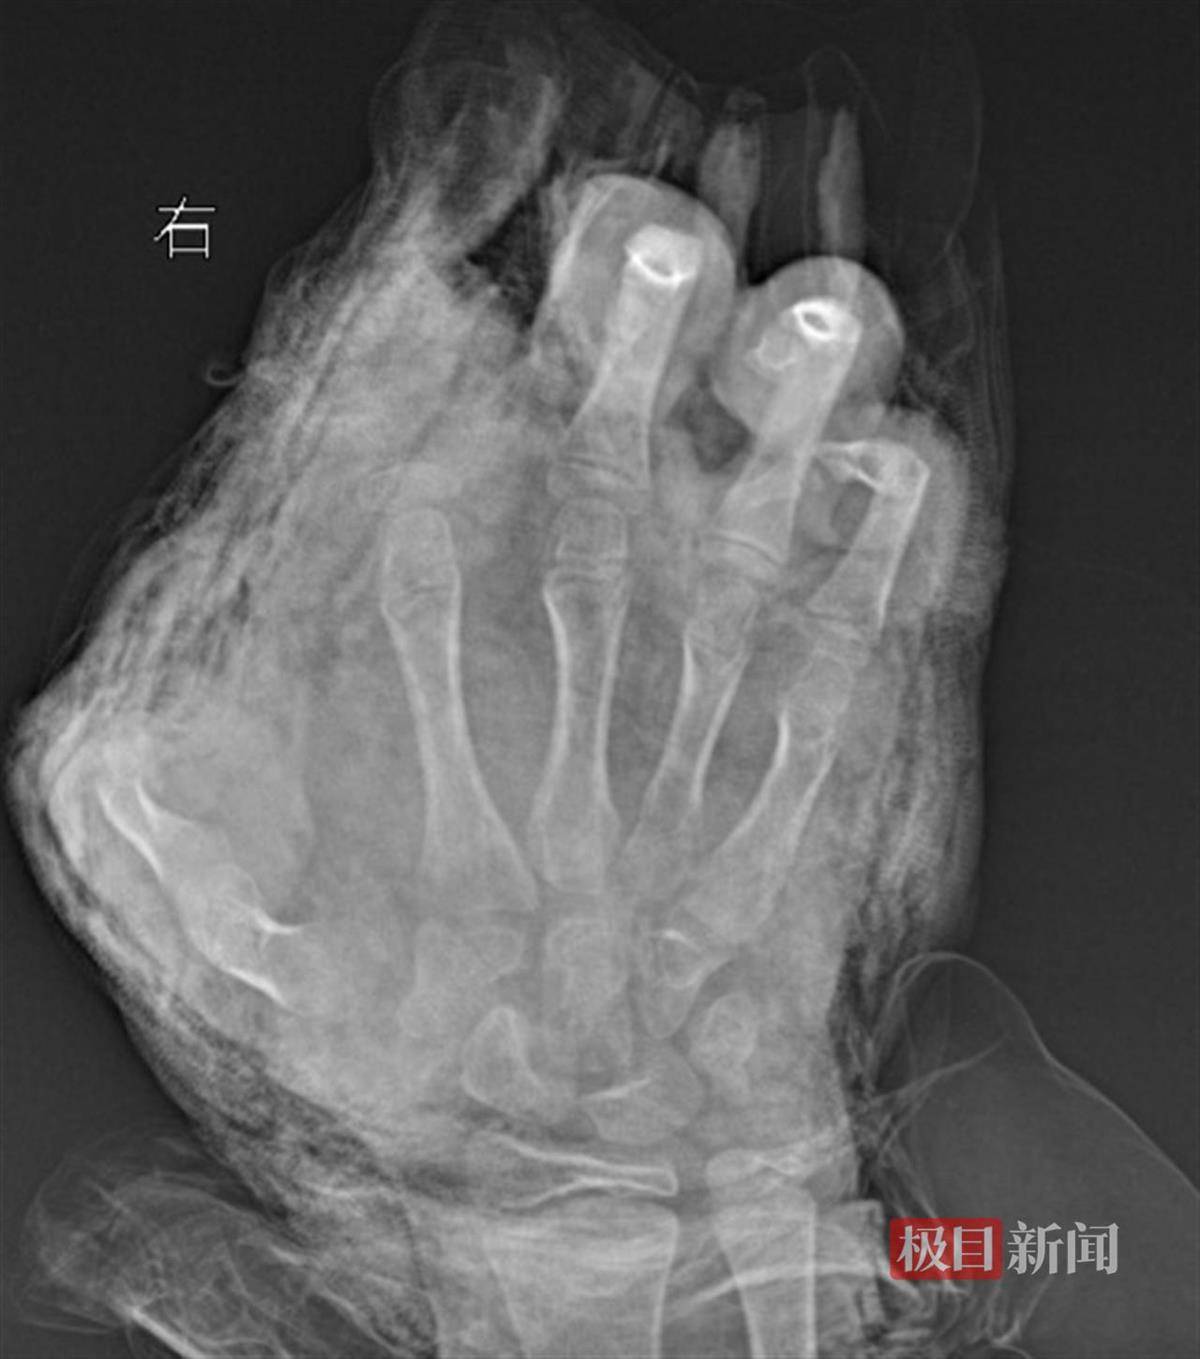

明明右手影像图

“孩子来院时,伤得触目惊心。”武汉市第四医院小儿创伤及矫形中心副主任医师徐剑介绍,初诊时看到明明双手血肉模糊,脸上和胸前均有炸裂伤,右手伤得最重,虎口处的伤口中还嵌入了小石子。经进一步检查发现,明明右手虎口处裂伤至手腕处,右手食指完全离断,拇指前段二分之一处被炸断,中指远节软组织缺损,环指和小指指腹炸伤严重。